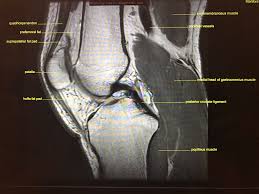

Magnetic resonance imaging (mri) is a noninvasive test used to diagnose medical conditions. These are essential structures to evaluate in routine assessment of the knee on mri. Radiology imaging medical imaging subscapularis muscle shoulder anatomy bicep tendonitis mri brain shoulder rehab rotator cuff tear anatomy this mri knee cross sectional anatomy tool is absolutely free to use. Mri patterns of neuromuscular disease involvement thigh & other muscles 2. Free access interactive and dynamic anatomical atlas. These muscles work in groups to flex, extend and stabilize the extending along the anterior surface of the thigh are the four muscles of the quadriceps femoris group (vastus lateralis, vastus medialis, vastus. Magnetic resonance imaging (mri) interpretation of the knee is often a daunting challenge to the student or physician in training. Which are the ligaments that keep it stable? An understanding of normal anatomy and biomechanics of the knee extensor mechanism is necessary to comprehend the imaging of extensor mechanism injuries. Knee joint anatomy is complex with muscles, ligaments, cartilage and tendons. General anatomy and musculoskeletal system. This section of the website will explain. Use the checklist to quiz yourself.

Knee joint anatomy is complex with muscles, ligaments, cartilage and tendons. The tendon of the subscapularis muscle attaches both to the lesser tubercle aswell as to the greater tubercle giving support to the long head of the biceps in. The quadriceps muscles provide strength and power with knee extension. This webpage presents the anatomical structures found on knee mri. Learn about the muscles, tendons, bones, and ligaments that comprise the knee joint anatomy. Please email baodo at stanford.edu. This mri knee cross sectional anatomy tool is absolutely free to use. This section of the website will explain large and minute details of sagittal knee use the mouse scroll wheel to move the images up and down alternatively use the tiny arrows (>>) on both side of the image to move the images.

Mri for evaluating knee pain in older patients: The muscles that affect the knee's movement run along the thigh and calf. Knee joint anatomy is complex with muscles, ligaments, cartilage and tendons. Each anatomical structure was labeled interactively. How does the knee joint work? Please email baodo at stanford.edu. The knee joint is most significantly affected by two major muscle groups: These muscles work in groups to flex, extend and stabilize the extending along the anterior surface of the thigh are the four muscles of the quadriceps femoris group (vastus lateralis, vastus medialis, vastus. Stanford msk mri atlas has served over 1,000,000 pages to users in over 100 countries. Robin smithuis and henk jan van der woude. Which are the ligaments that keep it stable? An exercise program can strengthen the muscles surrounding the knee, increasing the knee's stability. Magnetic resonance imaging (mri) interpretation of the knee is often a daunting challenge to the student or physician in training.

This webpage presents the anatomical structures found on knee mri. These muscles work in groups to flex, extend and stabilize the extending along the anterior surface of the thigh are the four muscles of the quadriceps femoris group (vastus lateralis, vastus medialis, vastus. Find out how the different structures fit together in our knee diagram the knee joint is the largest and one of the most complex joints in the human body. Normal anatomy, variants and checklist. How does the knee joint work?

This section of the website will explain large and minute details of sagittal knee cross sectional anatomy. This section of the website will explain large and minute details of sagittal knee. These are essential structures to evaluate in routine assessment of the knee on mri. This section of the website will explain. Learn everything about the anatomy and function of the knee now at popliteofibular ligament: Anterior graphic of the shoulder. Knee anatomy francesc malagelada jordi vega pau golanó the knee is the largest joint in the human body and one of the most complex from a functional point of view. Find out how the different structures fit together in our knee diagram the knee joint is the largest and one of the most complex joints in the human body.

They are attached to the femur (thighbone), tibia (shinbone), and fibula (calf bone) by fibrous tissues called ligaments. The journal of musculoskeletal medicine. Current and accurate information for patients about magnetic resonance imaging (mri)of the knee. Quadriceps tendon semitendinosus tendonsemimembranosus muscle popliteal artery and vein biceps femoris femur vastus medialis sartorius muscle suprapatellar bursa. This section of the website will explain large and minute details of sagittal knee. Scroll through the structures to understand the anatomy. Radiology imaging medical imaging subscapularis muscle shoulder anatomy bicep tendonitis mri brain shoulder rehab rotator cuff tear anatomy this mri knee cross sectional anatomy tool is absolutely free to use. An understanding of normal anatomy and biomechanics of the knee extensor mechanism is necessary to comprehend the imaging of extensor mechanism injuries. 4, infrapatellar fat pad of hoffa. Find out how the different structures fit together in our knee diagram the knee joint is the largest and one of the most complex joints in the human body. Located on the posterolateral aspect of the knee joint, extending from the popliteus muscle to the medial aspect of the fibula. Radiology imaging medical anatomy human anatomy and physiology anatomy study. The muscles that affect the knee's movement run along the thigh and calf.